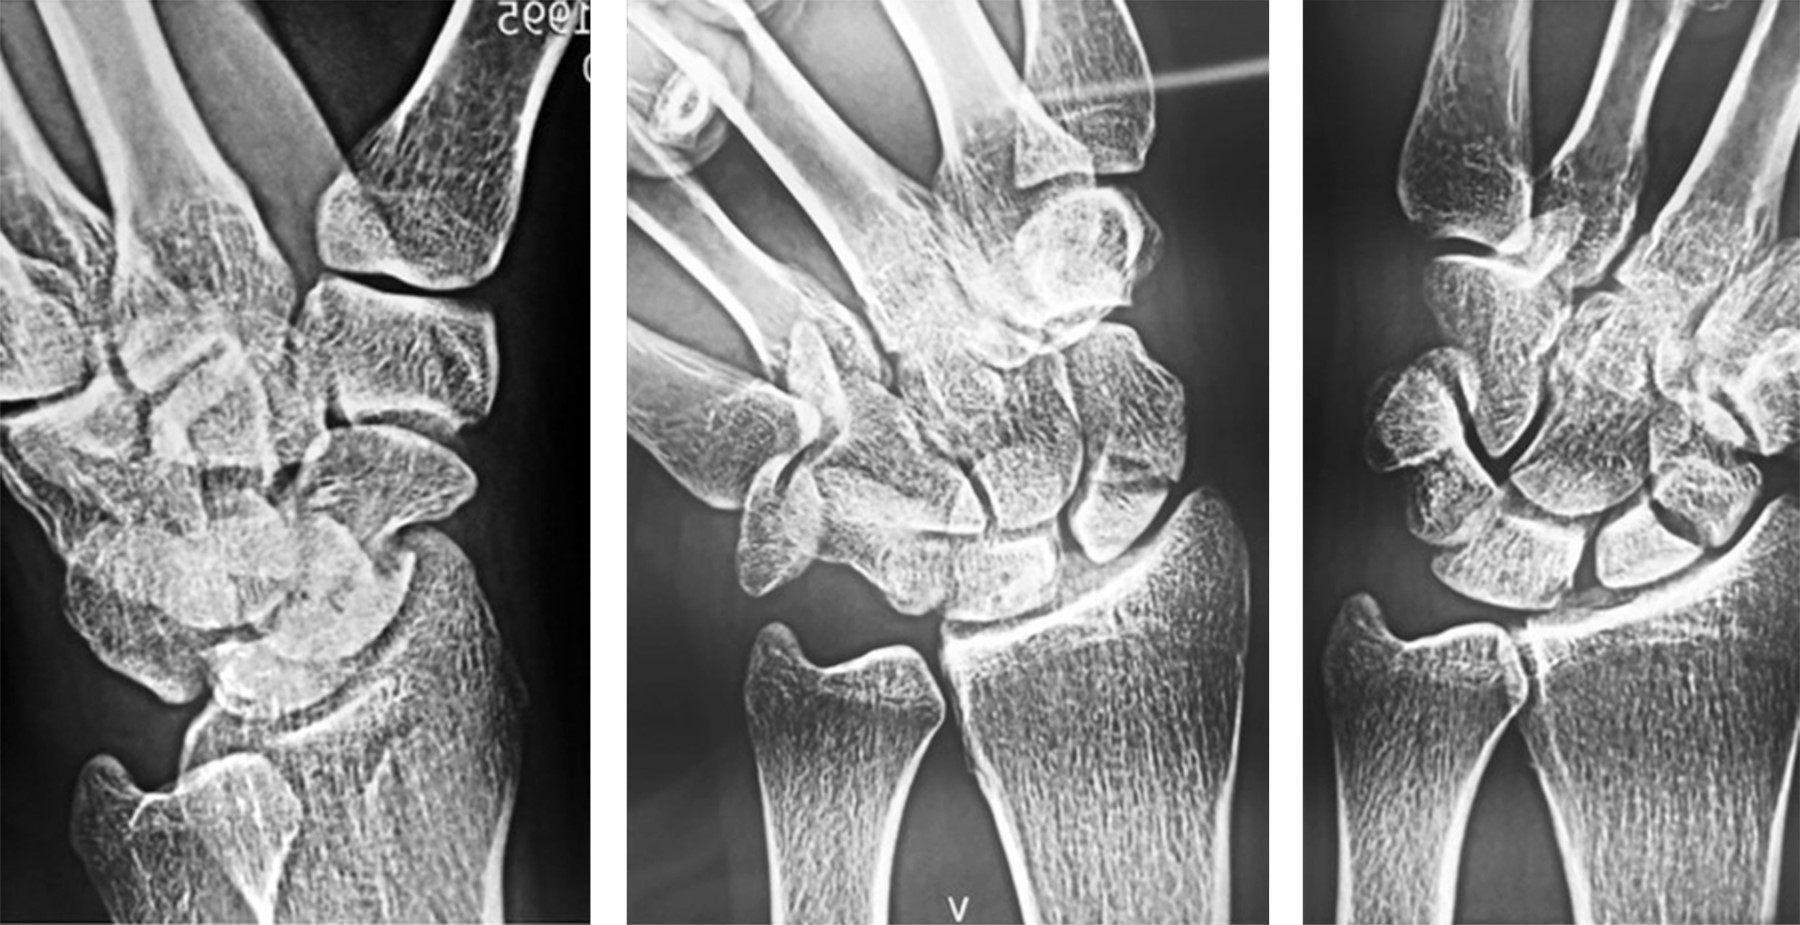

Todas las fracturas se encontraron en la cintura del escafoides y fueron catalogadas mediante la clasificación de Herbert y Fisher propuesta en 19846 utilizando radiografías anteroposterior, lateral y oblicua de muñeca (Figura 1). Una de las fracturas se clasificó como seudoartrosis (tipo D2) y las tres restantes como no unión fibrosa (tipo D1). Tres presentaron inestabilidad dorsal del segmento intercalado y dos deformidad en joroba del escafoides.

Figura 2